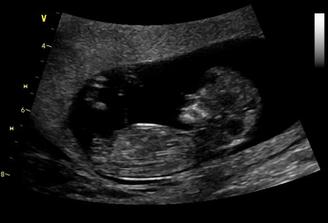

06/10/ bije srdííčko !!!!

16+1 geneticka konzultace OK,nemusíme na AMC

Zaplatila jsem si ale přesto UTZ a vypada to,že budeme mit chlapečka 🙂) pry tak na 80% jistota je vždy až po porodu 🙂)

CHLAPEČEK POTVRZENY Dr Břeštákem ))